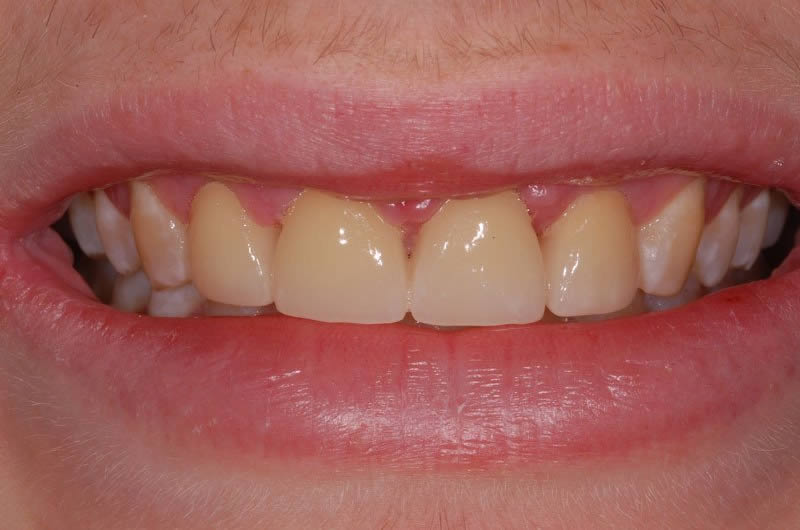

Case Studies

Dental Crowns (7 images)